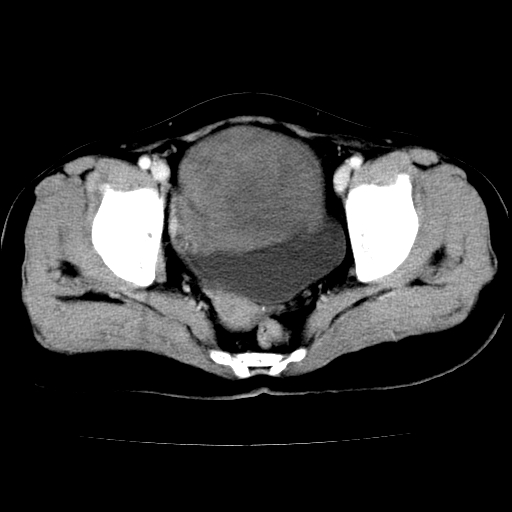

标题: CT24785:女,62岁,发现下腹部肿物半年。 [打印本页]

女,62岁,发现下腹部肿物半年,下腹部不适。

考虑子宫平滑肌肉瘤可能性大。

实性成分太多,要是囊腺瘤也要考虑恶性。